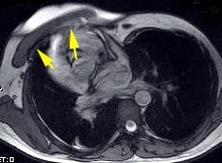

Tumor desmoide (“Fibromatosis agresiva”)

T1: Isointensos con músculos.

T2: Señal intermedia y de alta intensidad.

Presencia frecuente de áreas curvilíneas y lineales dentro de la lesión

Mansour J et al. Diagnostic and Imaging Approaches to Chest Wall Lesions. Radiographics 2022